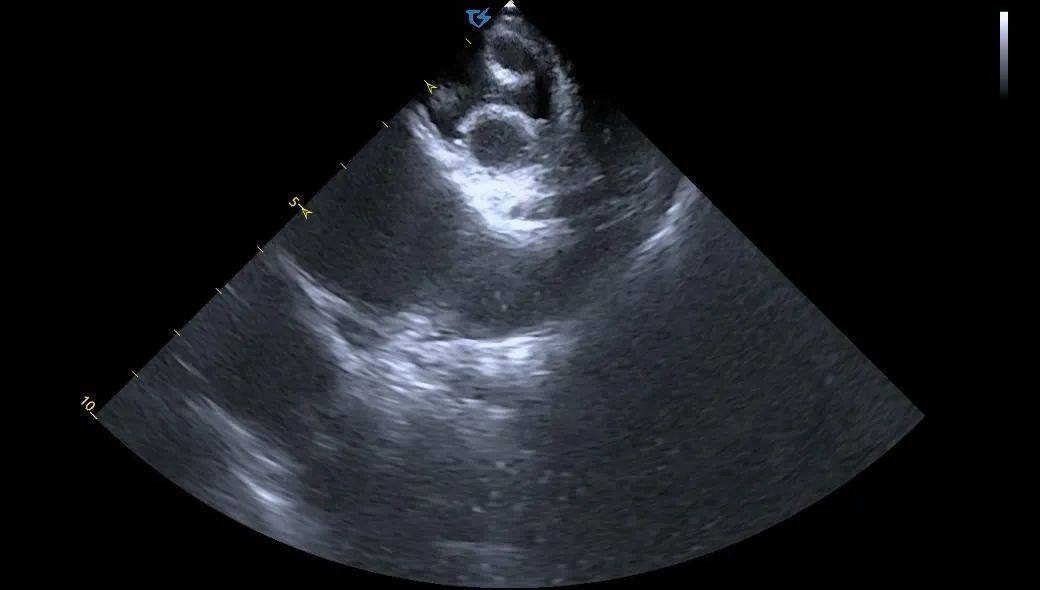

术前ICE左房血栓筛查

术中ICE指引导丝到上腔静脉

ICE直视下进行房间隔穿刺

穿刺后打水确认